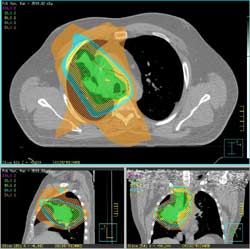

또한 폐암 치료에서도 주변 정상 폐 조직의 손상을 최소화하면서 종양에 방사선을 정밀하게 조사하는 것이 필수적입니다. 이를 위해 입체적 방사선 치료(3D CRT)와 같은 고급 방사선 치료 기법이 사용됩니다. 해당 방법은 정밀한 이미지 처리 기술을 활용하여 종양의 형태와 위치를 정확히 판단하고, 이를 기반으로 방사선 치료 계획을 세웁니다. 이를 통해 필요한 부위에만 집중적으로 방사선을 전달함으로써 주변 정상 조직의 방사선 노출을 획기적으로 줄일 수 있습니다.